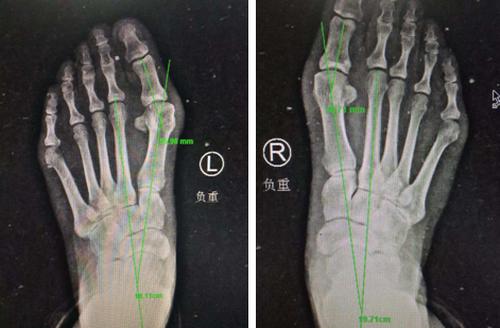

术前X线

3月11日上午,我院石荣剑院长为她做过体检和相关影像检查后,考虑患者二次手术,恐惧开大切口,决定为患者实施微创踇外翻矫正术。

石院长介绍,我院整形美容科采用韩国进口低频超声微磨锯实施颌面整形美容手术,切口很小,4毫米微磨锯锋利、精准、自带注水降温。受到启发,足踝外科创造性地将其优点运用到踇外翻微创治疗中去:不到1厘米切口无需缝合;微创截骨自带降温会更好的保护骨骼血运,从而截骨处会更快的愈合。

3月13日上午,石院长和足踝团队在足踝1:1模型上进行了缜密的术前设计。

石荣剑院长为李大姐进行了双足踇外翻矫形术。麻醉师采用超声引导下神经阻滞,手术团队采用不到一厘米切口,4毫米进口超声磨锯微创截骨,手术全程无血渗出,完美修整踇外翻。